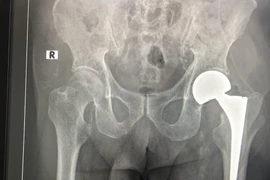

SuperPath là một trong kỹ thuật thay khớp háng tiên tiến nhất hiện nay. Phương pháp này được chỉ định phẫu thuật rộng rãi các bệnh lý khớp háng khác nhau như: hoại tử chỏm xương đùi, thoái hóa khớp háng, gãy cổ xương đùi...

Thay khớp háng nhân tạo ở người cao tuổi luôn là một trong những thách thức đối với kíp gây mê và phẫu thuật viên. Mới đây, khoa Chấn thương chỉnh hình đã thay khớp háng nhân tạo thành công cho cụ bà 107 tuổi.

(khoahocdoisong.vn) - Bệnh viện Chợ Rẫy TPHCM đã phối hợp đa chuyên khoa tiến hành phẫu thuật thay khớp cổ xương đùi thành công cho 1 trường hợp lớn tuổi - bệnh nhân N.T.K. (106 tuổi). Đây là bệnh nhân lớn tuổi nhất được thay khớp cổ xương đùi tại Bệnh viện Chợ Rẫy TPHCM.